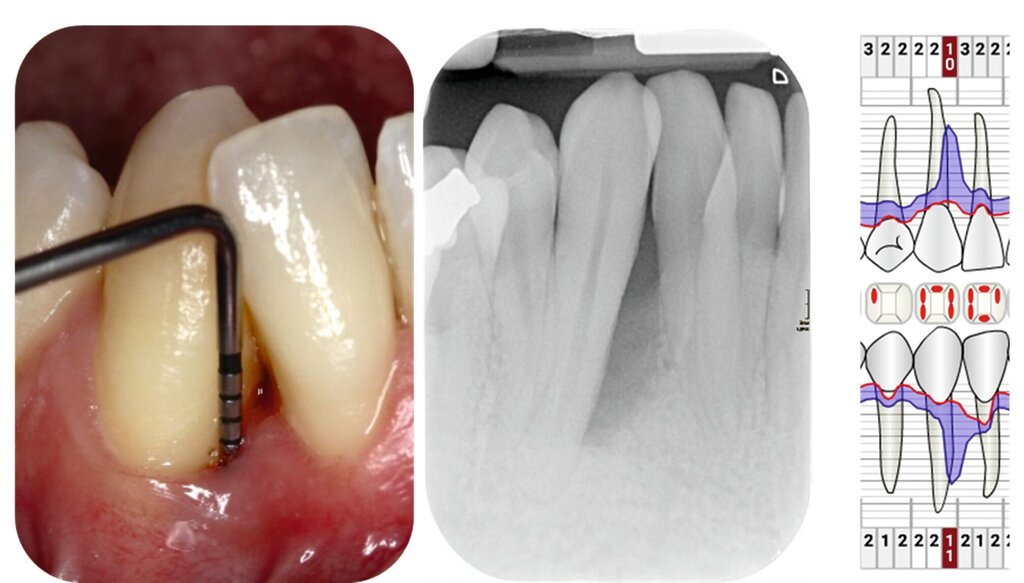

Die parodontale Regeneration ist eine gute Therapiemöglichkeit, um die Prognose von stark betroffenen Zähnen mit tiefen Resttaschen und Knochendefekten oder Furkationsdefekten zu verbessern. Der zusätzliche Nutzen für den Attachmentgewinn liegt bei durchschnittlich 1,34 mm und für die Reduktion der Sondierungstiefen bei 1,2 mm [Nibali et al., 2020]. Eine gute Plaquekontrolle wirkt sich dabei positiv auf das Heilungsergebnis aus und sollte deshalb die Basis für alle parodontalchirurgischen Maßnahmen sein [Rosling et al., 1976]. Auch Zähne mit Furkationsbefall sollten in die Parodontaltherapie einbezogen werden. Bei Furkationen von Unterkiefermolaren Grad II und Oberkiefermolaren mit bukkalem Furkationsbefund Grad II sollten regenerative parodontalchirurgische Maßnahmen in Betracht gezogen werden [Jepsen et al., 2020]. Zur Unterstützung der Regeneration von Knochentaschen oder Furkationsbefall Grad II stehen gut untersuchte Biomaterialien wie Membranen oder Schmelz-Matrix-Proteine mit oder ohne Zusatz von Knochenersatzmaterial zur Verfügung [Nibali et al., 2020]. Die Abbildungen 1 bis 3 zeigen einen Fall, bei dem durch eine regenerative Parodontalchirurgie die Prognose des Zahnes maßgeblich verbessert wurde.